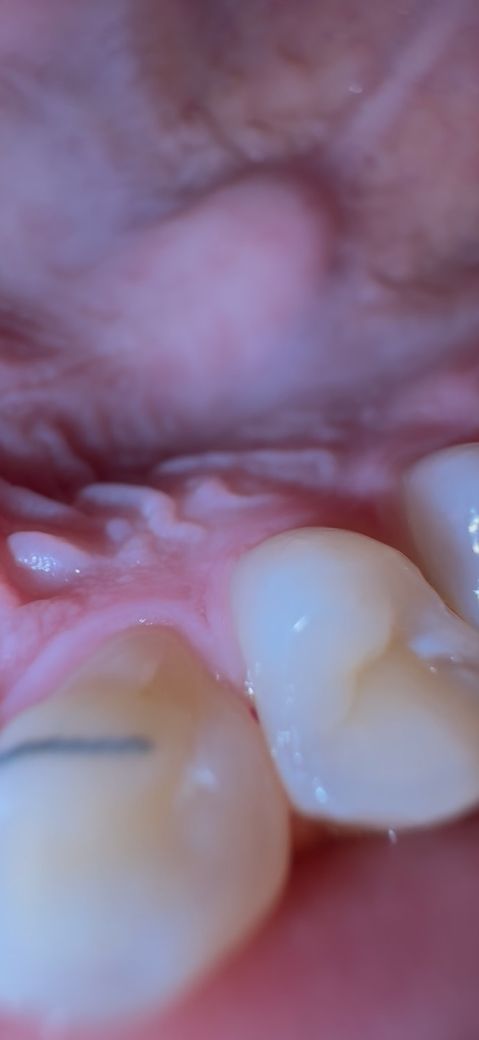

첫번째 사진은 위이빨 오른쪽 맨뒤 (사랑니는 아님) 어금니입니다.. 한달전에 치과가서 충치치료하고 덧대었는데 검은색 구멍같은게 생겼네요ㅎ휴ㅠㅠㅠ 충치겠죠? 아니 충치 심한것 같다고 했는데 제대로 치료 안해주더니 ㅠㅠ 여기는 평소엔 하나도 안 아픈데 아까 좀 만져보니 살짝씩 통증이 약간 있어요

• 1번 째 사진

사진상에 보이는 충치는 심한 충치는 아니고 간단한 충치인거 같으니 치과에 가셔서 간단히 치료하시면될것같습니다.

1. 첫번째 사진은 충치로 보여지지 않습니다 교합조정하면서 생긴 교합점이거나 음식물 이물질 아닐까 생각됩니다